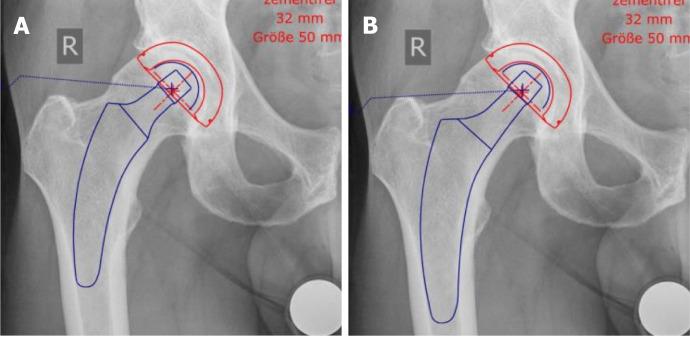

Short stems in total hip arthroplasty (THA) are becoming increasingly popular. In Germany, already 10.4% of all primary THAs are performed using a cementless short stem. The concept of modern, calcar-guided, short stems aims for an individualized reconstruction of the hip anatomy by following the calcar of the femoral neck, a bone- and soft-tissue-sparing implantation technique, and physiological loading. The stem design uses either metaphyseal fixation alone or additional diaphyseal anchoring, depending on the stem alignment and indication. These individualized anchorage types increase the potential indications for the safe use of a short stem. The design features may account for potential advantages of current short stem implants compared with earlier short-stem designs, particularly in cases of reduced bone quality or osteonecrosis of the femoral head and femoral neck fractures. The implantation technique, however, requires distinct knowledge regarding the characteristics of varus and valgus positioning, with the potential for clinical consequences. A learning curve for surgeons new to this technique must be taken into account. Cortical contact with the distal lateral cortex appears to be crucial to provide sufficient primary stability, and the use of intraoperative imaging to identify "undersizing" is highly recommended. Current results of several national registries indicate that calcar-guided short stems are among the most successful implants in terms of mid-term survivorship. However, long-term data remain scarce. This review introduces the characteristics of calcar-guided short-stem THA and summarizes the current evidence.